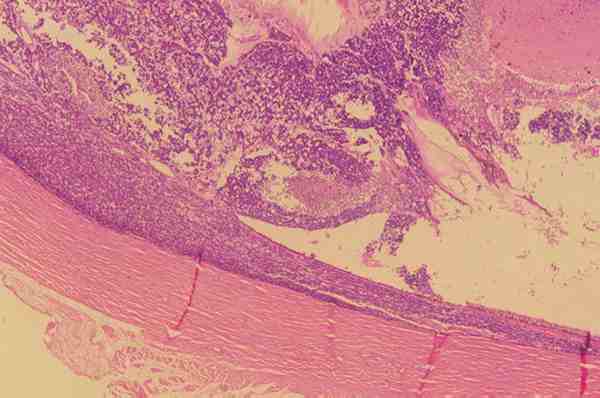

Frecuentemente sobretodo en un Retinoblastoma endofítico se produce una

diseminación vítrea que puede empeorar el pronóstico (figura 3).

Figura 3. Imagen macroscópica de un retinoblastoma endofítico con

diseminación vítrea.